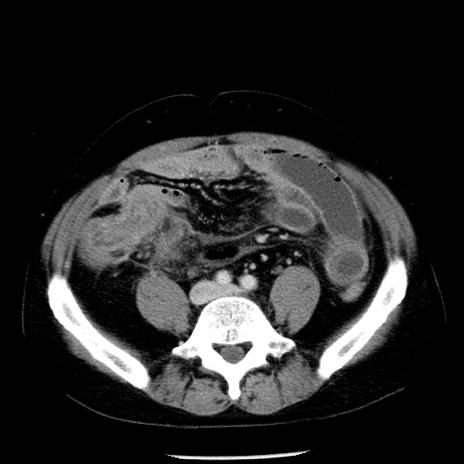

症例29(横断像)

【症例】40歳代男性

【現病歴】2日前から胃痛あり。徐々に周期的な激痛に変化した。本日になっても激痛があるため受診。

【身体所見】意識清明、BT 38-39℃台あり、腹部:膨満、やや硬、右下腹部に圧痛あり。

【データ】WBC 8500、CRP 23.26